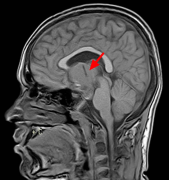

颅咽管瘤 是一种少见的中枢神经系统(CNS)良性肿瘤,被认为是由脑垂体附近的Rathkes囊残余形成。它们占全部原发性中枢神经系统肿瘤的不到1%,但却是儿童...

如果肿瘤很大,会导致垂体附近的其他神经或动脉受压,是将眼睛与大脑连接的视神经。颅咽管瘤本身不是垂体瘤,而是在垂体腺附近及其上方,在将眼睛...

颅咽管瘤能活多久?颅咽管瘤是在儿童或成年期期间诊断出的少见鞍区肿瘤,多发生在分泌多种激素的垂体附近...